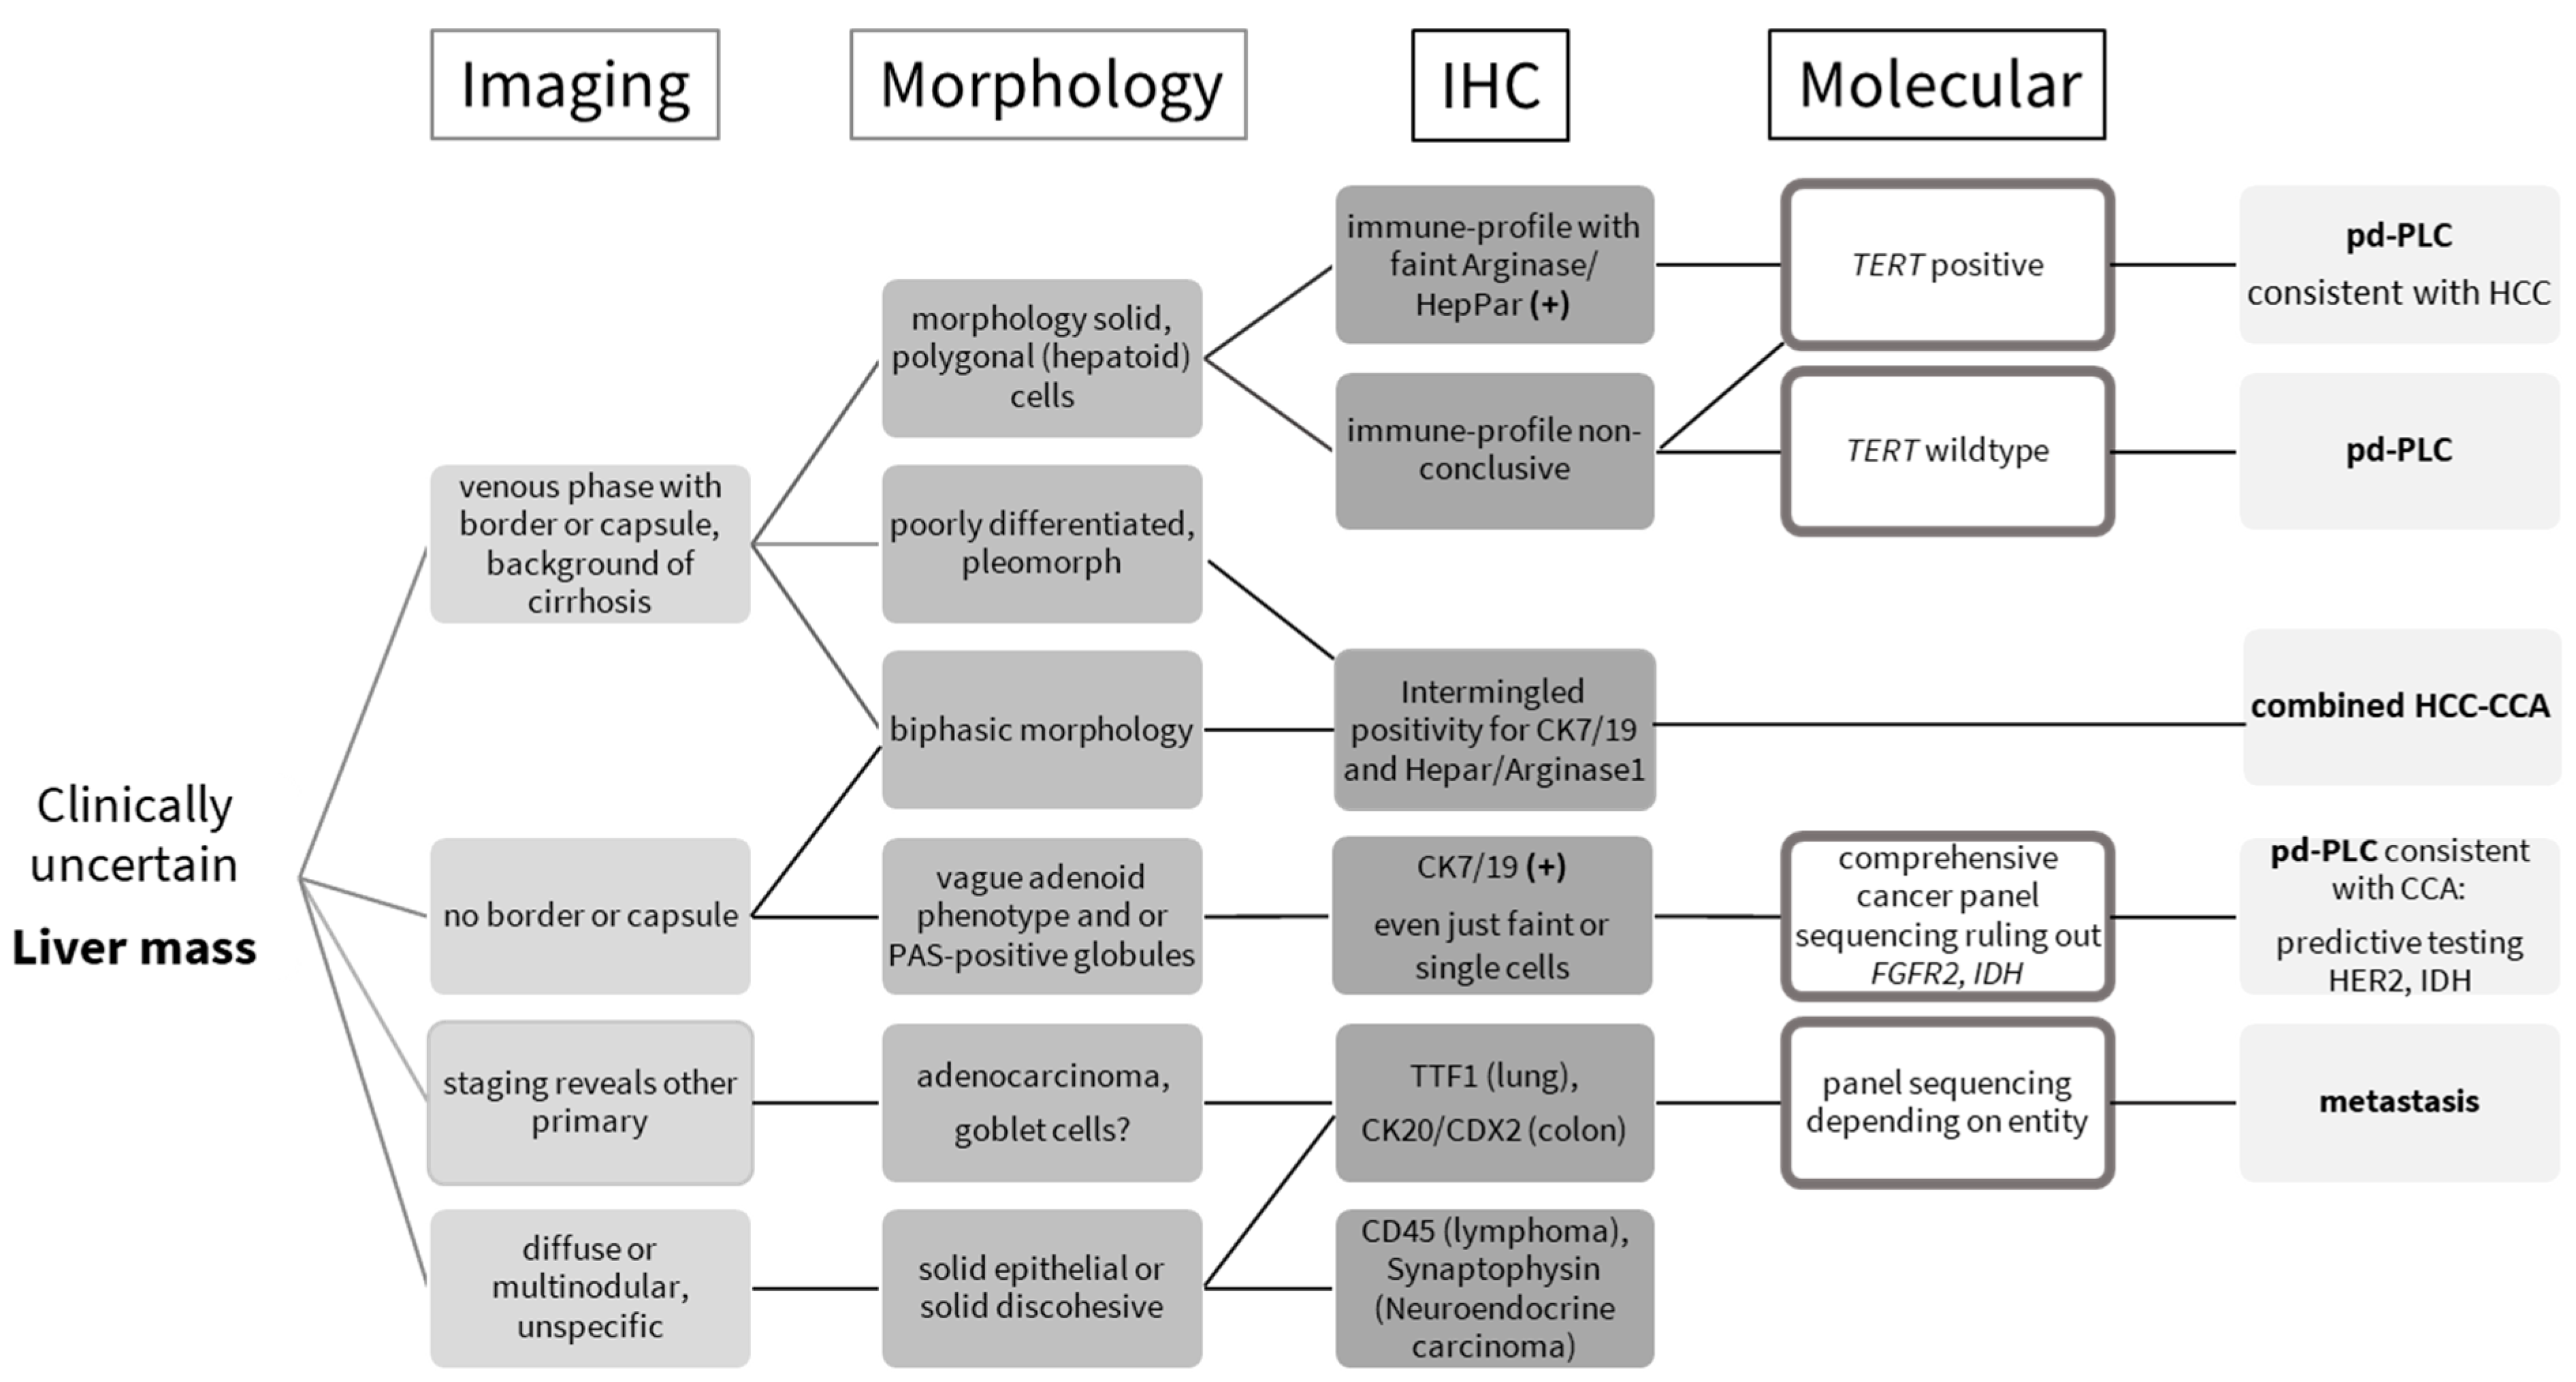

Clinically Uncertain Liver Masses: A Guide to Distinguishing Poorly Differentiated Primary Liver Cancer

Abstract

1. Introduction

2. Materials and Methods

3. Results

4. Discussion